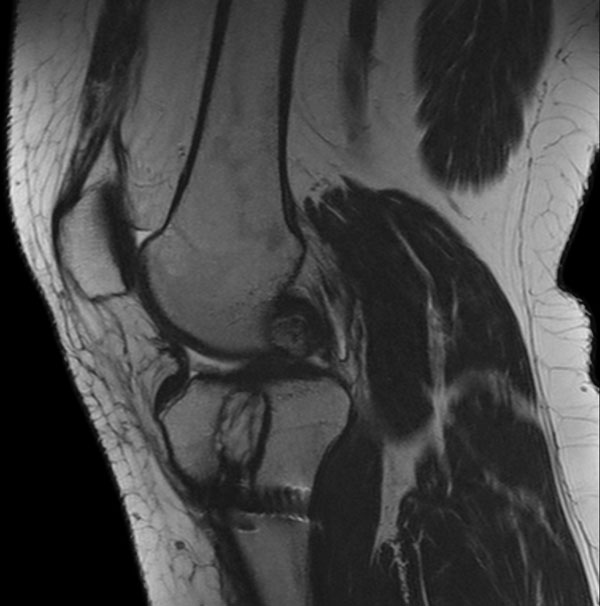

Sagittal T2w TSE

Sagittal T2w TSE (MARS)